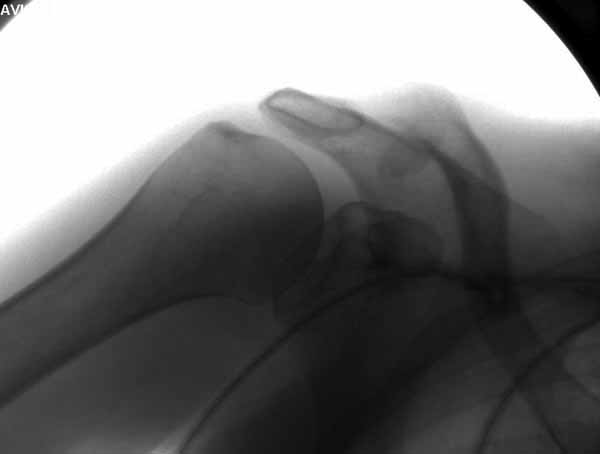

Из заданного вопроса в этом посте я понял, что разговор идет по поводу “методики применения ключичной пластины с крючком при акромиальных переломах”, т.е не ведется разговор “по поводу лечения косых переломов ключицы”.

Если так, тогда Юрий прав, методов лечения акромиона пластинами нельзя было найти. Обычно изобретали из реконструкционных пластин 2.7 или 2.4 мм толщиной. Такая фиксация адекватно удерживает перелом акромиона. Только недавно компания Acumed создала пластину для переломов акромиона, здесь линк: http://www.acumed.net/sites/default/files/literature/brochure-surgical-technique/CPS00-11-A.pdf.

По поводу пластины с крючком, Ваше заключение "не вижу препятствий для фиксации акромиального косого перелома ключицы для МОС использовать пластинку с крючком" вызывает сомнение.

Предназначенную для лечения повреждений связочного аппарата акромиально-ключичного сочленения пластину можно применить не при всех переломах акромиального конца ключицы. Потому что имплант рассчитан на интактную ключицу и не для переломов ключицы. Пластина короткая, не покрывает медиальный диафизарный фрагмент ключицы и за счет тракции стерноклеидомастоидеус такая фиксация прорвется через несколько дней.